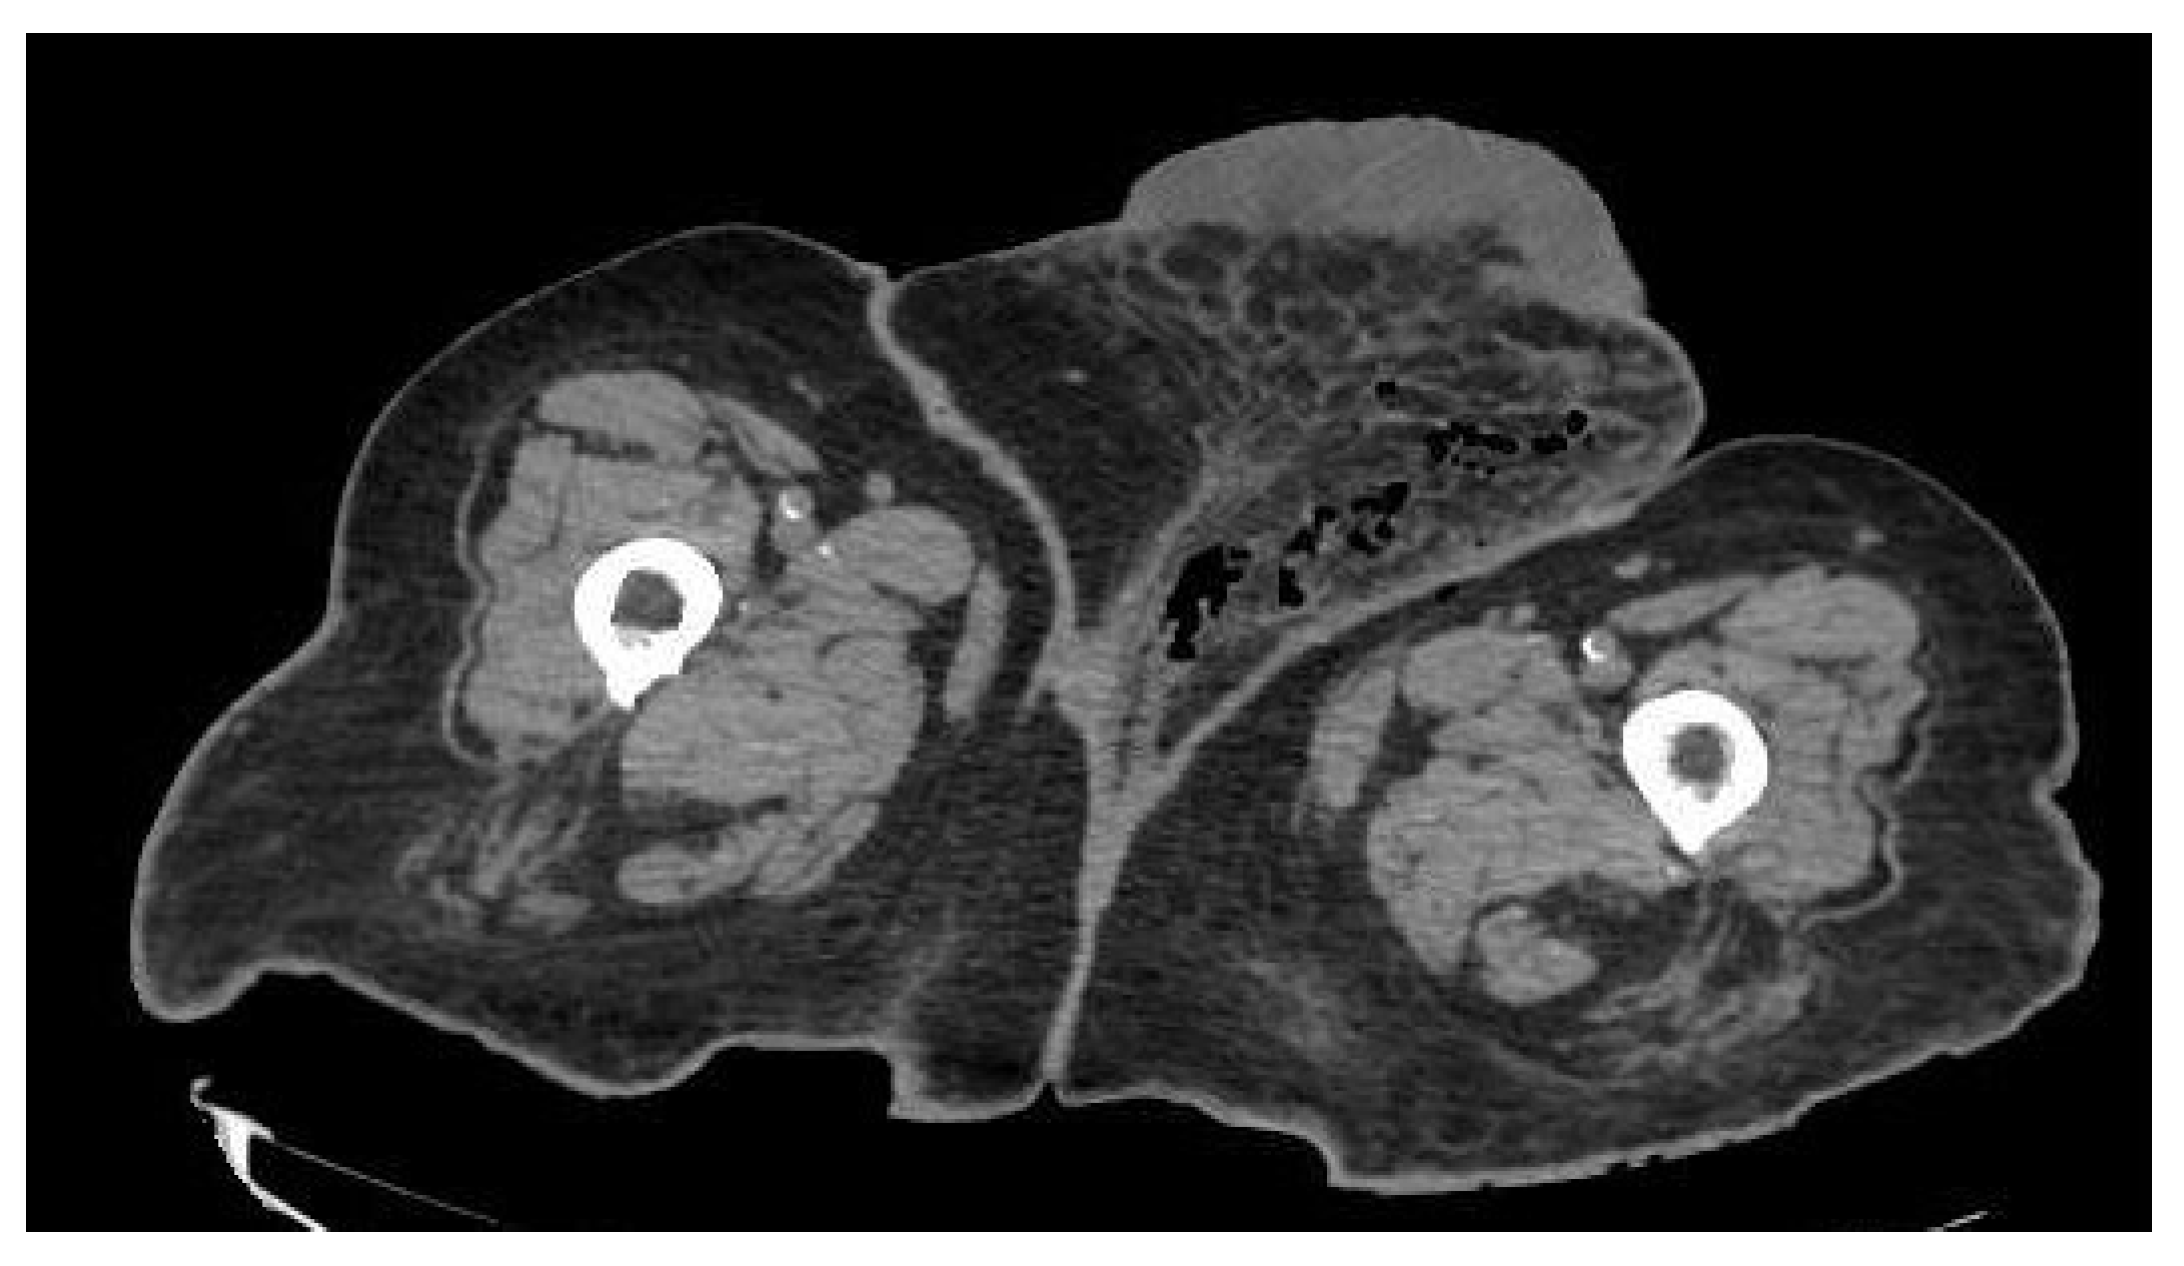

During the examination, she was in good general condition: normal blood pressure, only the temperature of 38 °C stood out. Blood tests showed slight anemia (hemoglobin 10.8 g/dL), normal platelets, marked leukocytosis 24,280/L with 92.8% neutrophilia. Normal coagulation times. Glomerular filtration decreased by 28%, creatinine 1.83 mg/dl (in accordance with her monorenal status). CRP 220 mg/dl. A CT showed soft tissue emphysema extending from the left labia majora to the mons Venus and left inguinal region. They were seen some thickening and trabeculation of fatty tissues around perineum and left femoral region. Radiological findings compatible with FG (Figure 4).

Figure 4.

CT of the abdomen and pelvis showed a FG which involves a soft tissue emphysema extending from the left labia majora to left femoral region, associated to a thickening and trabeculation of fatty tissues around them.